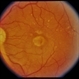

By Michael P. Kelly, FOPS

Duke University Hospital - Uploaded on Sep 14, 2012.

- age-related macular degeneration (AMD)

- Michael P. Kelly, FOPS Director, Duke Eye Center Labs, Duke Universtiy Hospital

Fundus camera

Zeiss FF450